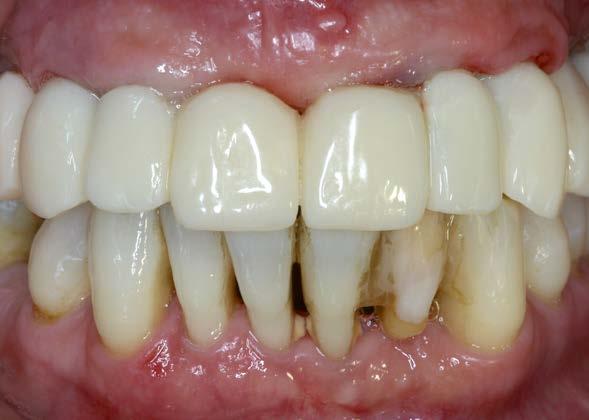

Se presenta el caso de una paciente de sexo femenino, de 55 años, que acude a consulta portando una prótesis removible superior anclada a un molar remanente correspondiente a la pieza 17, la cual presenta una marcada pérdida ósea. El resto de las piezas dentales habían sido previamente extraídas debido a enfermedad periodontal. La paciente solicita una alternativa a su prótesis actual, ya que no satisface sus necesidades estéticas ni funcionales.

En la radiografía inicial (Figura 1) se observa la pieza 17 con pérdida ósea significativa, así como una reabsorción ósea homogénea a lo largo de todo el arco superior. En la arcada inferior se aprecia pérdida ósea horizontal generalizada y defectos localizados, como una lesión en cuña en la pieza 46. Ante esta situación, se decide realizar la exodoncia del molar remanente del

arco superior y planificar una rehabilitación implantosoportada para todo el maxilar superior, así como para el extremo distal del tercer cuadrante.

La paciente continúa en seguimiento tanto de los implantes como de los dientes remanentes, bajo un estricto protocolo de mantenimiento periodontal. Durante el primer año el tratamiento se mantiene estable; sin

Figuras 10 y 11. Prótesis definitiva colocada en la paciente.

embargo, los incisivos inferiores presentan progresiva movilidad y pérdida de inserción. Luego de 2 meses se observa un incremento de la movilidad acompañado de dolor, por lo que se decide la exodoncia de los 4 incisivos inferiores, así como de la pieza 47.

La paciente continúa bajo seguimiento periodontal. A los 5 años se observa estabilidad clínica del tratamiento (Figuras 22–24), sin recesiones gingivales ni pérdida ósea asociada en las imágenes clínicas y radiográficas.

El mantenimiento periodontal y la implicación de la paciente en las medidas de autocuidado se mantuvieron de forma constante durante 23 años (Figura 25). La ortopantomografía realizada en una de las visitas de control mostró estabilidad completa de los implantes, sin signos radiográficos de pérdida ósea patológica.

Un año más tarde, al finalizar el periodo de seguimiento (24 años), las fotografías intraorales evidenciaron ligeras alteraciones de los tejidos blandos, con pequeñas troneras abiertas,

más evidentes en los dientes naturales conservados que en las restauraciones implantosoportadas. A pesar de estos cambios, el resultado global se consideró satisfactorio desde el punto de vista funcional y estético, especialmente en comparación con la situación clínica y radiográfica inicial previa al tratamiento (Figuras 26–31).